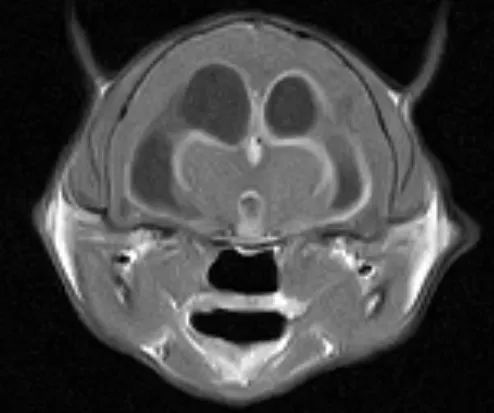

猫传腹是一种冠状病毒引起的感染性疾病。之所以被称为冠状病毒,是因为这类病毒在电子显微镜下,会呈现如日冕般外围的冠状。在所有冠状病毒中,最大名鼎鼎应该是这次的新冠病毒(SARS-CoV-2)。实际上,冠状病毒是自然界很常见的病毒,其中绝大多数并不致命,自然界中感染冠状病毒的猫也有很多,而在猫身上比较常见的一类冠状病毒是肠道的冠状病毒(Feline Enteric Coronavirus Virus , FECV),单纯的FECV感染,通常猫会出现拉稀等消化道问题,但过段时间就会自然痊愈。冠状病毒是一种RNA病毒,非常容易变异,同一只猫体内可能同时存在几种冠状病毒。大多数突变几乎不会改变冠状病毒的生物学行为。然而,有几个位置的突变可能会就是另外一回事了。某些突变会敲掉或者抑制冠状病毒上一个特定的基因,这种情况下猫传腹病毒(FIP Virus, FIPV)就出现了。FECV几乎只存在肠道内,但是FIPV会通过巨噬细胞和单核细胞在身体里游走,离开肠道,进入肾脏、腹膜以及中枢神经系统。在5个感染过FECV的猫中,就有1个猫体内有突变产生的FIPV,不过只有一部分的FIPV会最终导至猫传腹。总结一下,感染冠状病毒不等于得了猫传腹,冠状病毒突变成FIPV也不等于得了猫传腹。

猫传腹分为湿性和干性两种,前者约占70%,主要症状就是猫肚子胀大(腹水),再加之精神萎靡以及食欲不振,如果有发现这些症状,就要赶紧带猫去动物医院了。腹水(包括一些猫会出现胸水)并非猫传腹病毒引起的,而是猫自身在对抗病毒过程中免疫反应产生的,由猫的腹部器官炎症产生的大量渗出液。

而干性猫传腹的初期表现不太明显,没有湿性传腹那种肚子胀大的表现,并且病情进展也比湿性缓慢,主要通过眼部和神经系统表现。如果发现猫出现眼睛的炎症,同时又有走路不稳、抽搐等症状,就要尽快带去医院看一下。因此简单地说,有腹水不一定是猫传腹,猫传腹也不是都有腹水。但是,如果2岁以下的猫突然出现肚子胀大,还是要高度警惕猫传腹。

主要症状上面有说,分为湿性和干性(还有一些混合的),不再赘述。在检测指标中,说几个重要的。李凡他试验:李凡他试验不能确诊是否是猫传腹,但这个检测的准确的还是比较高的。在小于2岁的猫中,李凡他试验阳性,确诊猫传腹的概率为88%。白球比(白蛋白/球蛋白比例,A/G):在传腹猫中,由于腹膜炎的缘故,白蛋白会降低,球蛋白会升高,因而白球比整体会降低。白球比也是判断治疗是否有效的标准之一,如果治疗有效,大多数猫的白球比应该上升。猫冠状病毒检测及猫冠状病毒突变位点检测:前者是通过PCR检测的办法,检测腹水中是否有冠状病毒,而后者是检测冠状病毒是否变异(成为传腹病毒)。如果检测到腹水中有冠状病毒并且有变异的话,几乎可以100%确诊猫传腹了。不过这两项检测一般需要几天至一周的时间出结果,大多数家长会在腹水的李凡他试验阳性后,就开始给猫进行治疗。对于医生来说,并非只看某一个指标就可以直接确诊,需要综合上述指标进行判断。